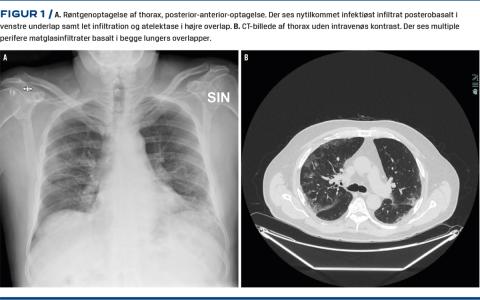

Ved indlæggelsen fandt man desaturation på 88% uden ilt, let forhøjet C-reaktivt protein-niveau på 47 mg/l, normalt leukocyttal og lymfopeni med lymfocyttal på 0,35 × 109/l. En røntgenundersøgelse af thorax viste bilateral lungeaffektion med infiltrative forandringer (Figur 1A). En supplerende CT af thorax viste spredte perifere basale matglastegninger bilateralt (Figur 1B). Patienten fandtes COVID-19-positiv den følgende dag. Efter syv døgns indlæggelse kunne han udskrives til eget hjem, uden at han havde haft behov for intensiv terapi i forløbet.

Ovenstående sygehistorie illustrerer de klassiske lungeforandringer, som oftest ses ved COVID-19. Hos patienten i sygehistorien fandt man perifer, bilateral lungeinvolvering på både røntgenoptagelser af thorax og den efterfølgende CT af thorax. På CT’en sås infiltraterne som matglastegning, hvilket er karakteristisk. På baggrund af de kliniske symptomer var patienten på forhånd podet for COVID-19, og denne podning viste sig at være positiv.